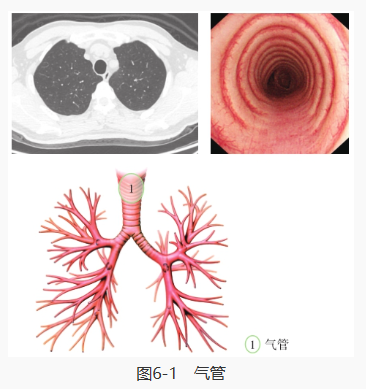

开始进行支气管镜检查,首先我们看到的是气管: